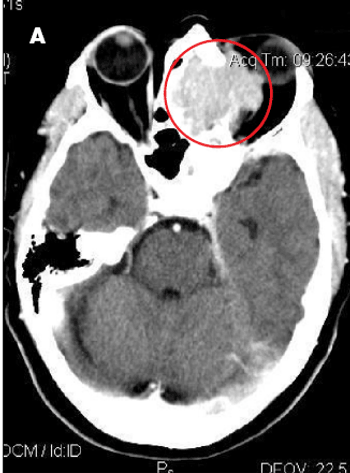

Progressively worsening nasal congestion and headaches with diplopia and left proptosis for 2 months prompted an ophthalmology consultation for a 67-year-old woman. She had been evaluated multiple times for allergic rhinitis and recurrent sinusitis.